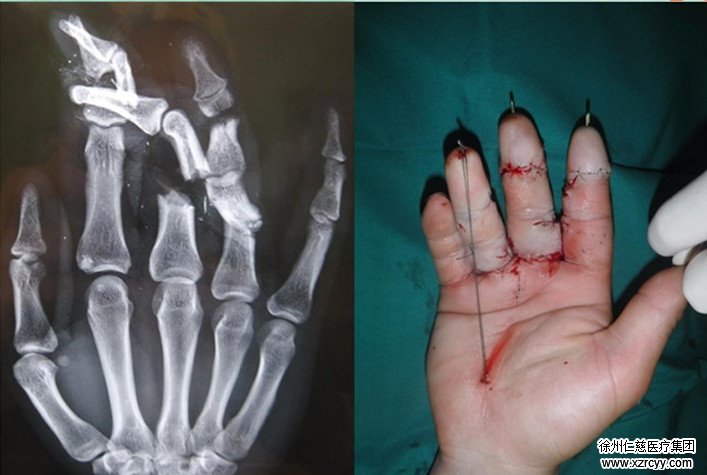

随后受伤的陈先生被紧急推往检查室进行检查,经检查,陈先生右手示、中、环指不全离断,血管神经肌腱受到严重损伤,需要紧急进行手术。经过几个小时的手术,陈先生的三根手指被成功接上,目前情况还需要进一步观察。

betway在线登陆手足显微外科熊祖国医生介绍,患者送来的时候肢体损伤很严重,血管都是断的,现在虽然手指被成功接上,但是能否成活,还需要观察。目前最主要风险有两方面,第一个是感染期的问题,因为他是绞肉机伤的,里面全部都是那种腐肉,还有油污,污染比较重。第二个是血管虽然接上了,但是恢复情况还要观察。一般十天左右,如果患者情况稳定的话,才算是过了危险期。